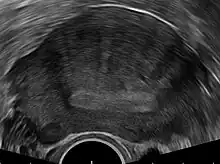

Transvaginal ultrasonography

Transvaginal ultrasound of the uterus, showing the endometrium as a hyperechoic (brighter) area in the middle, with linear striations extending upwards from it

Transvaginal ultrasonography is a cheap and readily available imaging test that is typically used early during the evaluation of gynecologic symptoms.[24] Ultrasound imaging, like MRI, does not use radiation and is safe for examination of the pelvis and female reproductive organs.[25] Overall, it is estimated that transvaginal ultrasonography has a sensitivity of 79% and specificity of 85% for the detection of adenomyosis.[11]